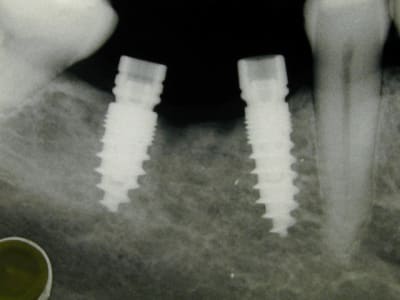

des photos d'un cas d'aujourd'hui avec le shuttle retiré ( 8 premières photos)

les 4 dernières c'est avec le foret , la dernière photo c'est un cas d'extraction implantation d'aujourd'hui aussi on voit la nouvelle alvéole après le forage ( désolé pour la qualité de photo...)

Une fraise diamantée sur une turbine chirgicale, aprés comme d'habitude. C'est une radio per-opératoire, je l'ai rentré 2 mm de plus. Tu les as essayés, les C?

Et une mandibule en MCI cet aprés midi. Comme tu vois ça ne saigne pas beaucoup.